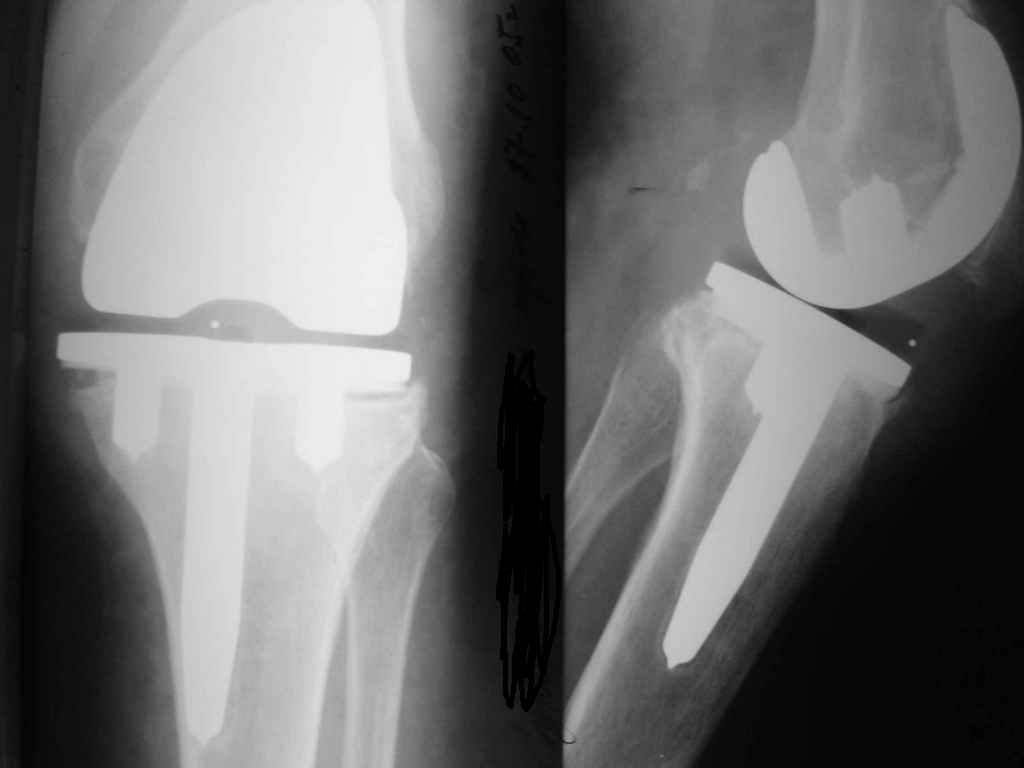

Уважаемые коллеги. Пациентка 65 лет соматически сохранна 6,5 месяцев назад выполнено замещениеколенного сустава интегральным эндопротезом Фримана Самуэльссона - цемент, по поводу ДОА. Послеоперационное течение с длительным субфебрилитетом. Местно без особенностей и выписана домой на 28 сутки с обьемом движений в колене 90 град. с частичной опорой. Дома отмечала субфебрильную лихорадку. Живет в небольшом поселке далеко от цивилизации. Контрольный осмотр в 3 месяца особых клинических проблем лечащий врач не нашел. Однако рентгенологически отмечены зоны остеопороза вокруг компонентов, на которые не обратил внимание. С 4 месяца отметила ухудшение - отек в колене, ограничение движений и боль. Лечилась у местного врача-хирурга (нестероиды и местно мазилки) - без эффекта. Обратилась только в 6,5 мес. Движения в суставе 20 град, отечность колена, выпот по УЗИ. Боль неопределенная, ходит с тростью. Лихорадки нет, в ан крови СОЭ 36 остальное норма, острофазовые тесты СРР повышен вдвое = 12 (при норме 6) Ревмотест - норма..Пункция - посев - роста не дает. Пробовали артроскопию - артрофиброз. Трудности осмотра из-законтрактуры и спаек. Рентгенограммы в динамике - в приложении (динамика с ухудшением). Вопросы:1. Инфекция? или остеопения местная? 2. Ревизия или подождать и полечить остеотропами? Благодарю заранее за любой совет. А Рыков. Хабаровск.

Показание к ревизии - нестабильность протеза (его компонентов) В приведённом Вами случае на Рг очевидная зона резорбции вокруг тибиального компонента следствие этого его нестабильность. Наиболее вероятна вялотекущая инфекция( судя по показателям крови и клиническим проявлениям: отек, боль, выпот и как следствие - ограничение функции)